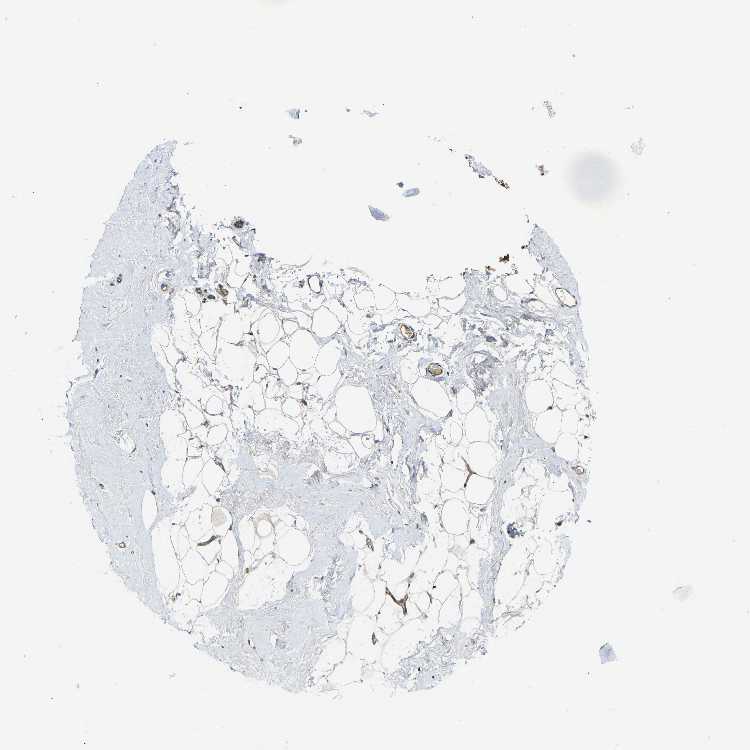

BREAST - Antibody stainingi

Antibody staining in the annotated cell types in the current human tissue is reported as not detected, low, medium, or high, based on conventional immunohistochemistry profiling in selected tissues. This score is based on the combination of the staining intensity and fraction of stained cells.

Each image is clickable and will lead to virtual microscopy that enables deeper exploration of all samples and also displays staining intensity scores, fraction scores and subcellular localization as well as patient and tissue information for each sample.

Antibody HPA001490Antibody HPA013616

Adipocytes Not detectedNot detected

Glandular cells MediumHigh

Myoepithelial cells MediumMedium